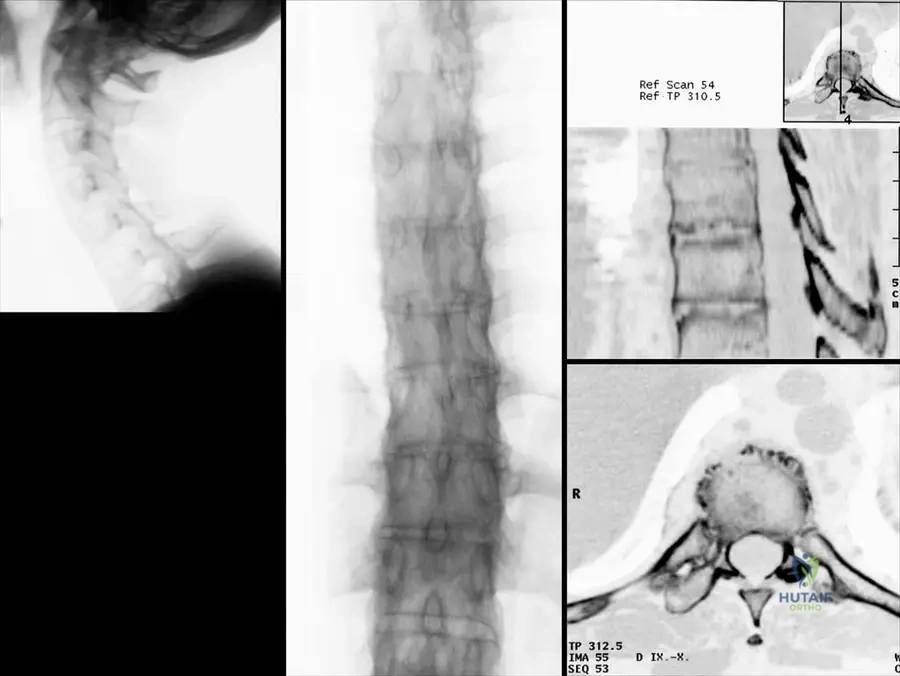

A 40-year-old male with long-standing Ankylosing Spondylitis presents with increasing spinal stiffness. A thoracic spine radiograph is obtained.

A 50-year-old male with advanced Ankylosing Spondylitis undergoes a CT scan of his lumbar spine due to increasing rigidity.

A 45-year-old male with a long history of Ankylosing Spondylitis presents with severe spinal stiffness. Lateral radiographs of his thoracic spine show extensive ossification of the anterior longitudinal ligament and annulus fibrosus, leading to a characteristic appearance. What is this radiographic appearance commonly referred to as?

View Answer & Explanation

Correct Answer: C

Rationale: Fig. 3.34b specifically labels the image as "Typical 'bamboo' appearance of the thoracic vertebral column." This term describes the extensive syndesmophyte formation and ossification that fuses the vertebral bodies, resembling a bamboo stalk. Romanus lesions (erosions at vertebral body corners), Andersson lesions (disc space inflammation/erosion), Dagger sign (ossification of supraspinous and interspinous ligaments), and Shiny corner sign (sclerosis at vertebral body corners) are other radiographic findings in AS but do not describe the overall fused spinal appearance.

A 38-year-old male with a known history of Ankylosing Spondylitis undergoes a lateral radiograph of his lumbar spine. The image reveals characteristic bony outgrowths bridging the vertebral bodies, originating from the outer fibers of the annulus fibrosus. What are these specific bony formations called?

Correct Answer: B

Rationale: Fig. 3.35a explicitly labels these as "Typical marginal syndesmophytes." Syndesmophytes are characteristic of spondyloarthropathies like AS, representing ossification within the annulus fibrosus, leading to spinal fusion. Osteophytes are typically seen in degenerative disc disease, enthesophytes refer to ossification at tendon/ligament insertions, spondylophytes is a general term for bony outgrowths, and Schmorl's nodes are intravertebral disc herniations.

A 40-year-old male with advanced Ankylosing Spondylitis undergoes a CT scan of his thoracic spine. The scan reveals erosions of the end-plates of the vertebral bodies and marginal syndesmophytes. What is the significance of these end-plate erosions in the context of AS?

Rationale: Fig. 3.34c shows "Reconstruction CT picture reveals erosions of the end-plates of the vertebral bodies and marginal syndesmophytes." These erosions (Romanus lesions or "shiny corners" on plain film) are inflammatory lesions at the vertebral body corners where the annulus fibrosus attaches, and they are considered precursors to the formation of syndesmophytes, which eventually lead to spinal fusion. They are not primarily signs of degenerative disease, osteoporosis, or infection.

A 55-year-old male with advanced Ankylosing Spondylitis undergoes a CT scan of his lumbar spine due to severe stiffness. The CT scan reveals bony union of the lumbar facet joints. What is the significance of this finding in AS?

Rationale: Fig. 3.35b shows a "CT scan of the lumbar spine: Bony union of the lumbar facet joints." This bony fusion of the facet joints is a characteristic pathological feature of advanced Ankylosing Spondylitis, contributing significantly to the severe spinal stiffness and immobility seen in the disease. It is not a normal age-related change, a sign of infection, or a rare finding, but rather a direct consequence of the inflammatory process.

A 48-year-old male with long-standing Ankylosing Spondylitis experiences increasing difficulty with deep breathing. A CT scan of his thoracic spine is performed, revealing bony fusion of the costovertebral joints. What is the clinical implication of this specific finding?

Rationale: Fig. 3.34d shows a "CT scan of a thoracic vertebra with bony fusion of the costovertebral joint." The costovertebral joints connect the ribs to the thoracic vertebrae, and their fusion directly restricts rib movement, thereby contributing to the decreased chest expansion, which is a hallmark clinical symptom and diagnostic criterion of AS. It is not directly related to neuropathy, hip pain, or spinal fracture risk, and it is certainly not asymptomatic in terms of respiratory mechanics.